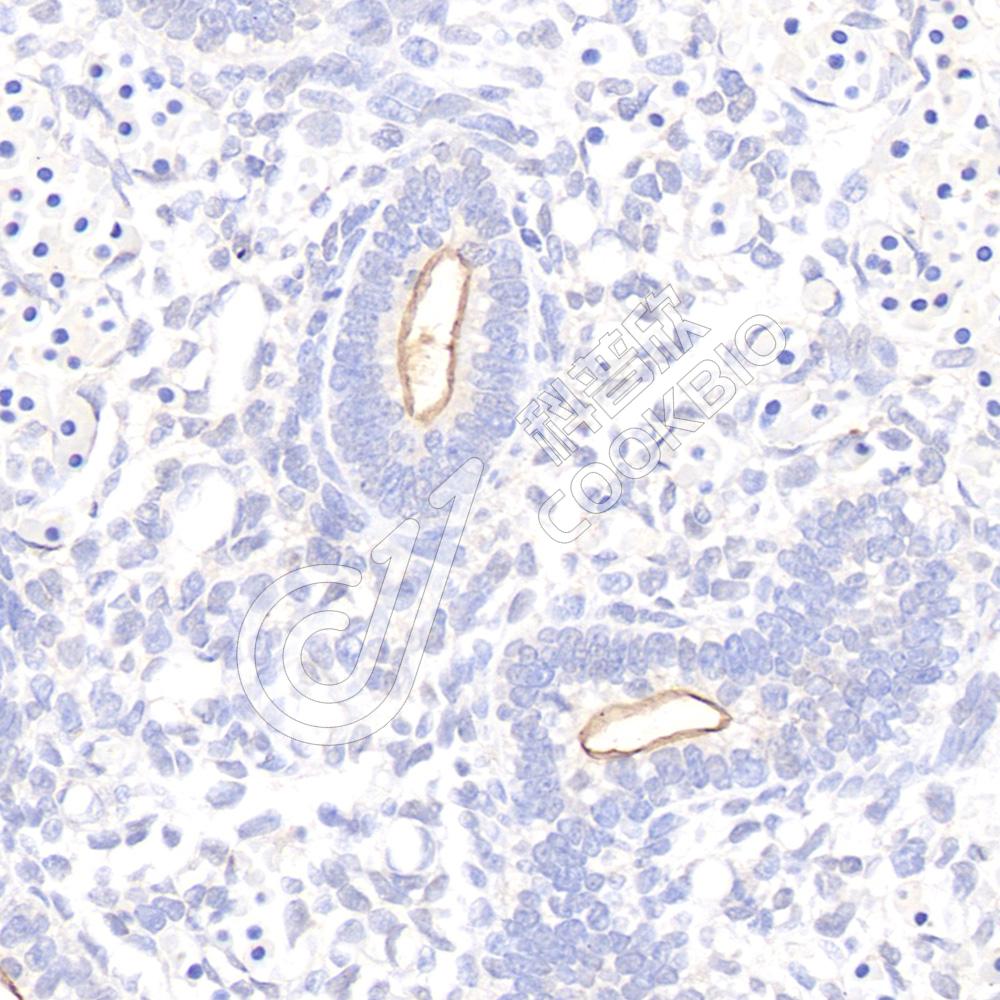

IHC检测CD133蛋白(货号 K1341421).

样品: 大鼠胎肺, 4%多聚甲醛 (货号KSG1101) 固定12-24小时.

抗原修复: 柠檬酸抗原修复液(干粉, pH 6.0) (KSG1201), 98℃, 20分钟.

—抗: 1: 1100稀释, 4℃ 孵育过夜.

二抗: S-vision免疫组化多聚二抗(山羊抗兔),即用型 (货号KB3906), 室温孵育20分钟.